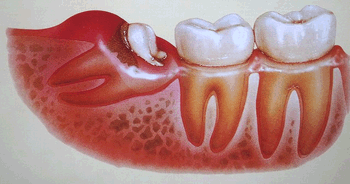

絵にすると、ちょうどこんな感じになります!

歯の根っこの部分は骨に埋まっているのですが、歯の頭の部分(エナメル質)には歯肉はくっつかないので、埋もれた「親知らず」の頭の周りは「歯周ポケット」のようなちょうど「袋 ふくろ」のような隙間があるのです! 当然ですが「食べカス」も入り、清掃不可能な不衛生な「汚れの首輪」になっているのです!

この影響で「親知らず」の周りの歯肉が「腫れたり」、「痛んだり」悪さをします!

また、かくれた歯の溝には虫歯も出来やすく、治療するのが困難な場所になります! |